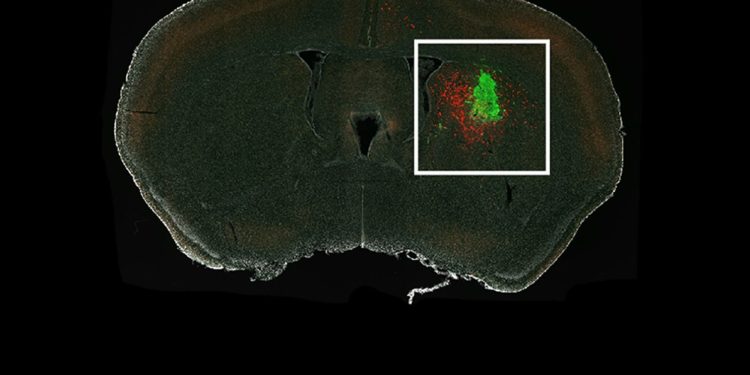

Researchers revealed which neurons in a mouse brain, shown in red, connect to a human glioma, shown in green.

Image: Annie Hsieh

Hsieh and team successfully traced the glioma-innervating neurons back to their sources using a rabies virus engineered to infect only specific cells of interest and to light up those cells when it gets in. The virus travels from the tumor cell back through the neuron that connects to it.

The researchers injected human glioma cells into the brains of mice and waited for neurons to connect with the tumors. They then applied the rabies virus to light up cells of interest. Soon, they had a picture illuminating the mouse brains showing all the glowing neurons that led to the glioma.

The maps revealed that the gliomas hook into existing patterns of neuronal wiring.